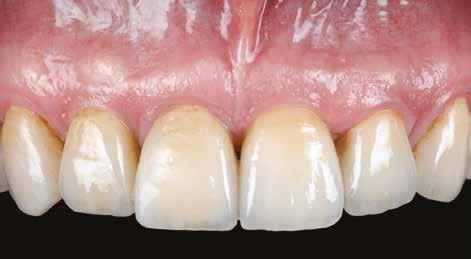

Hat hónappal az implantátum beültetését követően az implantátumokat feltárták, az emergencia-profilt ideiglenes fogpótlással alakították ki (9. a. ábra), majd 1 hónappal később a végleges fogpótlások is behelyezésre kerültek (9. b ábra) Intraorális röntgenfelvételek készítése is történt a végleges restaurátumokról a behelyezésükkor (10. a. ábra), és 12 hónappal később is, mindenfajta csontfelszívódási jel nélkül (10. b ábra)

10. ábra: (a) Intraorális röntgenfelvétel a végleges helyreállítás elkészítésének végén, (b) 12 hónappal az elkészítést követően.

Az 1. sz. táblázatban látható, az alveolus horizontális méretbeli csökkenése bekövetkezett, függetlenül az alveoláris gerinc prezervációjától, a mérsékelt horizontális zsugorodás egyik esetben sem zárta ki az implantátum beültetését Az alveolus horizontális méretbeli csökkenése 20,7% volt az alveolusok legkoronálisabb részén, 15,9% a koronális mérési vonal alatt 2 mm-rel, és 13,1% a koronális mérési vonal alatt 4 mm-rel A horizontális változásokkal ellentétben a vertikális dimenziók nem mutattak térfogatvesztést, inkább a defektusok szuprakresztális telődése következett be A vertikális dimenziók átlagos növekedése 6 hónap után – a kiindulási értékhez képest – 18,3% volt A szuprakresztális ATB-graftrészecskék megmaradtak, és láthatóan kapcsolódtak az újonnan képződött szubkresztális keményszövethez a reentry során végzett megfigyelésnél Mindazonáltal a szubkresztális területhez képest gyengébb szerkezeti integritás volt megfigyelhető A klinikus szemszögéből nézve, az ATB-grafttal prezervált területek konzisztenciája az implantátum csontfészkének készítése során közel állt a D3-D4 csonthoz A vékony biotipusú esetekben az implantátum feltárását követően, enyhe, kezdeti negatív remodellinget figyeltek meg� (10. a. ábra) A kresztális csont stabilitása a biológiai szélesség kialakulása után is megmaradt, amelyet a 12 hónapos után követéses vizsgálat során a röntgenfelvételek is megerősítettek (10. b. ábra)�

A vizsgálat során összesen 98 személyt kezeltünk a fentiekben ismertetett protokoll alapján Az implantátumok behelyezését követő 72 órán belül minden esetben fémkerámia pótlások kerültek átadásra Az elkészült rögzített fogpótlások végleges cementtel kerültek rögzítésre� Az okklúzió közben érintkező rágófelszínek a két kisőrlő fogon és az első nagyőrlő fog meziális részén kerültek kialakításra (1. ábra)

1. ábra: Palatinálisan elhelyezkedő kontaktfelszínek. A terhelési zóna kiterjedésének csökkentése érdekében a rágás közben érintkező rágófelszínek kizárólag a felső őrlőfogak palatinális csücskeinek megfelelően kerültek kialakításra.